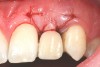

Fig 18. The final restoration after 4 months.

Figure 18

There are numerous scenarios when a papilla-sparing incision can be advantageously used, including implant placement, the reconstruction of soft tissue and bone, or both. Figure 10 through Figure 18 and Figure 19 through Figure 25 illustrate how papillae-sparing incisions can be used to restore form and function using a nonsubmerged implant protocol. (Surgeries were performed by DT.)

Fig 10. Case 2: Missing tooth No. 7 was extracted 3 months before implant placement.

Figure 10